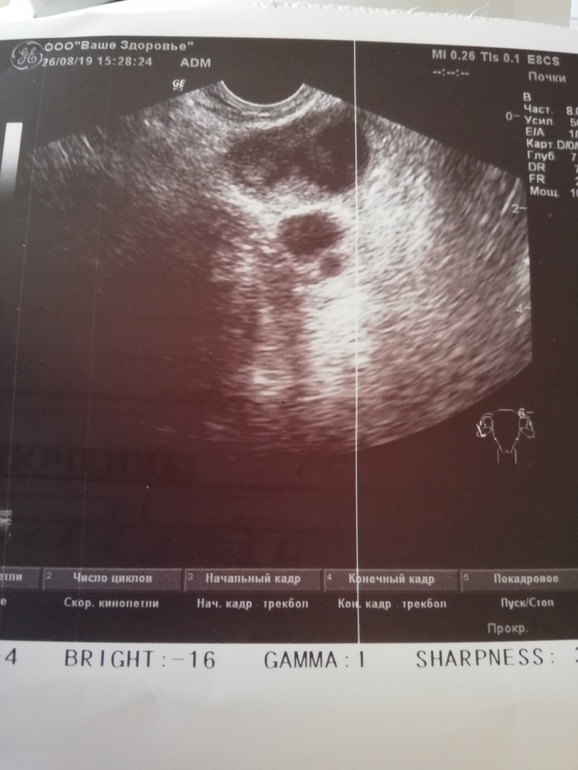

Здравствуйте девочки прошу помощи, вообщем на 14дмц,была на узи сказали что есть желтое тело 17мм, сейчас 22дмц пришла на узи сначала врач сказал что жт16 мм, рядом киста 17мм, а потом нет, мол это все кистозное желтое тело 30мм, 3 цикл отмены кок, в 1 месяце отмены была киста фолликулярная, в том месяце все чисто было, и вот сейчас вот так. Может быть переделать узи? Или что нибудь посоветуйте пожалуйста

Киста ЖТ, это ерунда, не страшно, выходит с М. Может дать задержку небольшую. Думаю не стоит переделывать вам УЗИ))